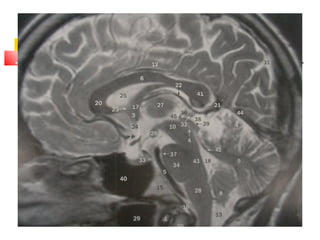

-Pineal bez 3. ve 4. ventrikülleri birleştiren

aquaductus sylvius’un başlangıcının hemen

üzerinde ve bir sapla 3. ventrikülün arka

duvarına bağlı bir organdır. Uzunluğu 5-9 mm,

çapı 3-6 mm, ağırlığı 100-180 mg civarındadır.